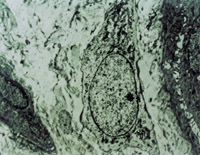

2. 電鏡觀察 受傷當(dāng)日上皮組織變性壞死,可見(jiàn)單核細(xì)胞核偏移、固縮,并有吞噬現(xiàn)象(圖5-3-12)。

5-3-12 燒傷當(dāng)日,單核細(xì)胞核偏移,固縮,并有吞噬現(xiàn)象  TE×8000